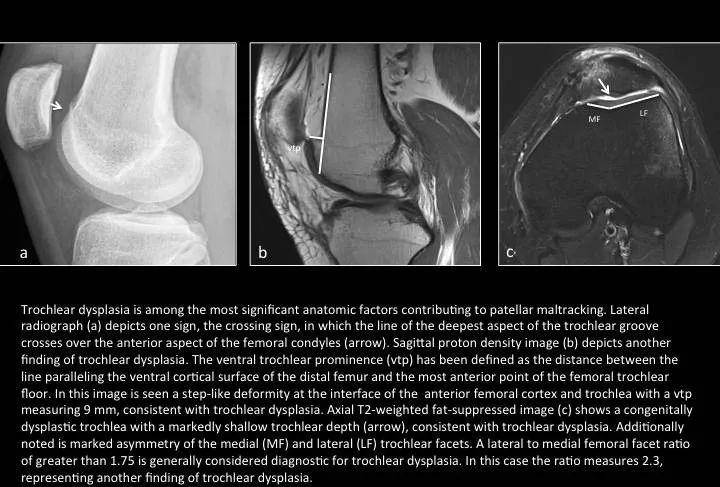

Fig. 9: Trochlear dysplasia

图9:(股骨)滑车发育不良

股骨滑车发育不良是指滑车沟前部的几何外形和深度存在的解剖学异常。可引起髌骨轨迹不良或慢性膝关节不稳。